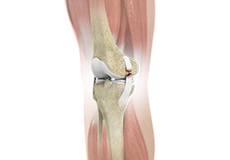

Unicompartmental/Partial Knee Replacement

Unicompartmental knee replacement is a minimally invasive surgery in which only the damaged compartment of the knee is replaced with an implant. It is also called a partial knee replacement.